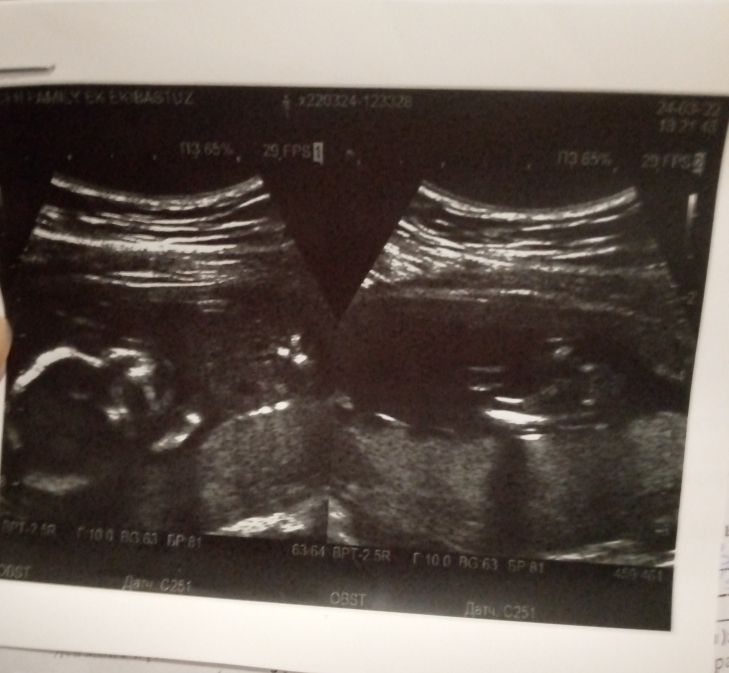

Сейчас на фото тазовое предлежание

В ожидании второго тигрёнка, скажите на 17 недели это норма?

В смысле как лежит? Головкой вниз/вверх? В любом случае эта информация мало зачем сейчас. Вы можете выйти с узи и ребенок перевернется) недели до 30-33 ребенок лежит как угодно)

Узи 4 нед.4 дня , двойня? Измерения шейки